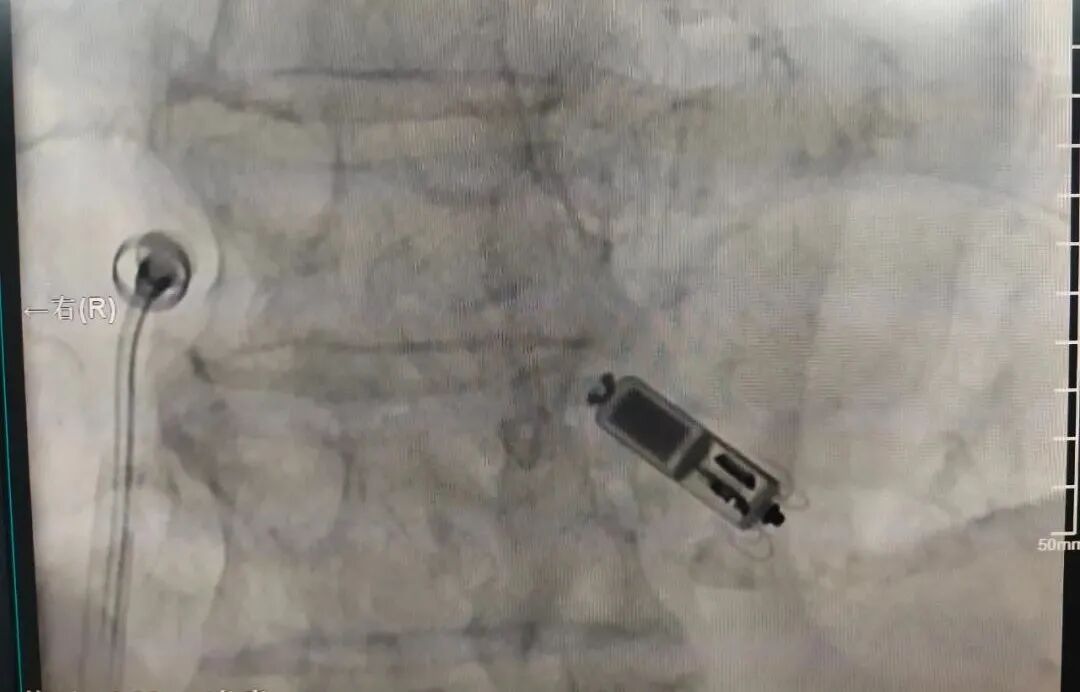

13日下午,楊飛主任帶領(lǐng)心律失常團隊為患者施行手術(shù)。在患者局部麻醉后,醫(yī)生穿刺右側(cè)股靜脈建立通路,將起搏器送入右心室,選定合適的位置,確認固定及工作參數(shù)良好,成功釋放后手術(shù)完成,用時僅1小時。整個過程中,患者始終保持清醒狀態(tài)。術(shù)后6小時拆除右股靜脈包扎繃帶,第二天即可下床自由活動。

Micra順利植入右心室開始工作